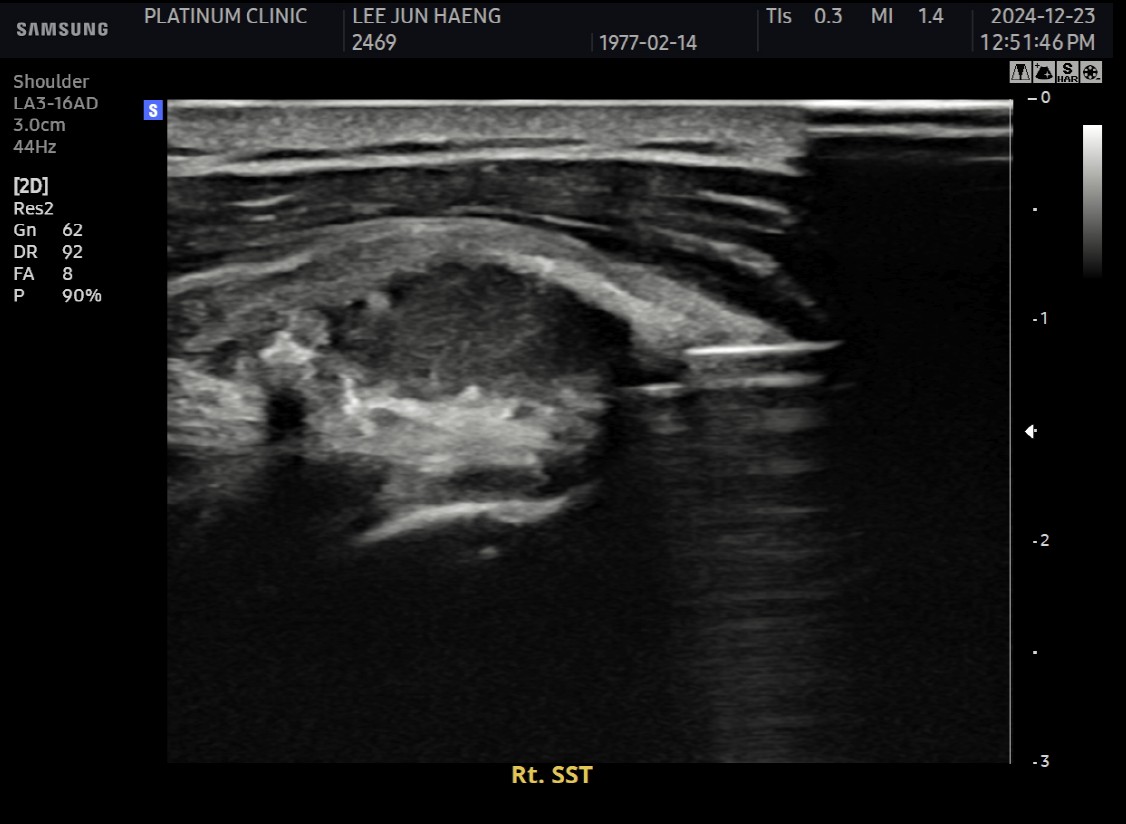

진단:

X-ray: 약 1.3cm 석회 (휴지기)

초음파: 석회 주변 인대 염증 소견

석회분쇄흡입술 시행

시술 시간: 35분